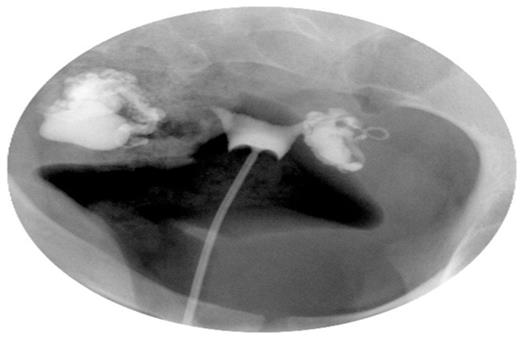

A 22-year old nulligravida presented with a history of primary infertility. Eighteen months prior to presentation, she was diagnosed with a chlamydial infection by cervical culture and treated with a single dose Azithromycin. A negative Chlamydia culture was confirmed four months prior to presentation. As part of her initial infertility evaluation at our center, a hysterosalpingogram (HSG) was performed in a window of Doxycycline prophylaxis which demonstrated bilateral hydrosalpinges, with the right tubal diameter measuring greater than the left and bilateral tubal occlusion (Figure 1).

Hysterosalpingogram demonstrating bilateral distal tubal occlusion with hydrosalpinges